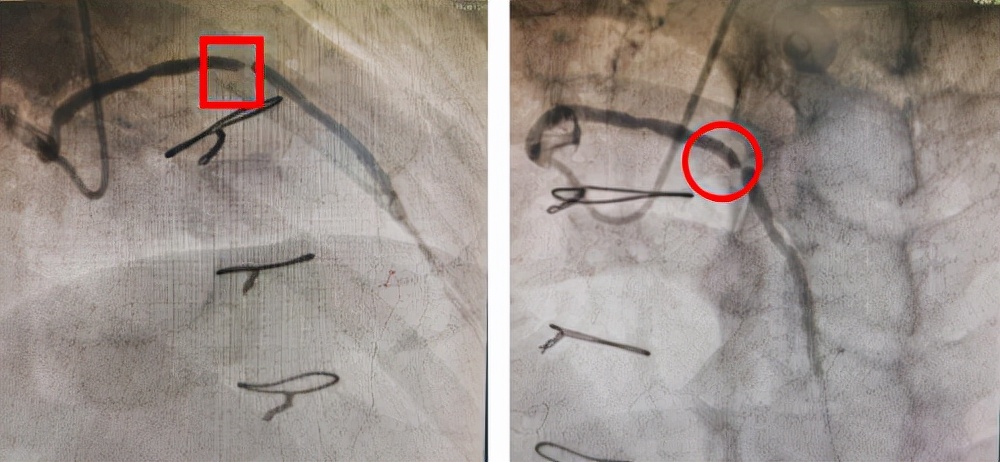

前降支静脉桥血管术前造影影像

前降支静脉桥血管药球治疗术后影像